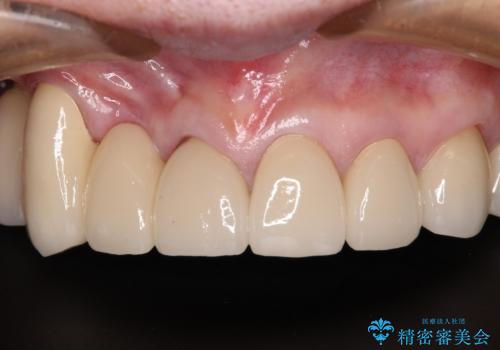

長く見える歯を治したい 歯肉移植による歯肉増大術

- 前歯を2本抜歯した後に装着した仮歯が長く見えるのが気になるとのことで来院された患者様です。

抜歯後には歯を支えていた骨が失われるため、歯肉が痩せてしまい、結果としてブリッジのダミーの歯を長くする必要があります。

前医では、歯肉の位置に相当する部分を、歯肉に近い色とすることで歯の長さが揃っているようにカムフラージュする治療が提案され、仮歯もそのようになっていました。

歯肉が痩せてしまっている状態を改善するため、口蓋から歯肉の結合組織を採取し、移植することで厚みを増大させることとし、その後オールセラミックブリッジにて補綴治療を行うこととしました。

1回の歯肉移植により歯肉の厚みは大幅に改善されましたが、折角なのでもう少し大きくしたいとの要望があり、2回目の処置も行うこととしました。

厚みも高さも十分な歯肉量を獲得することができました。